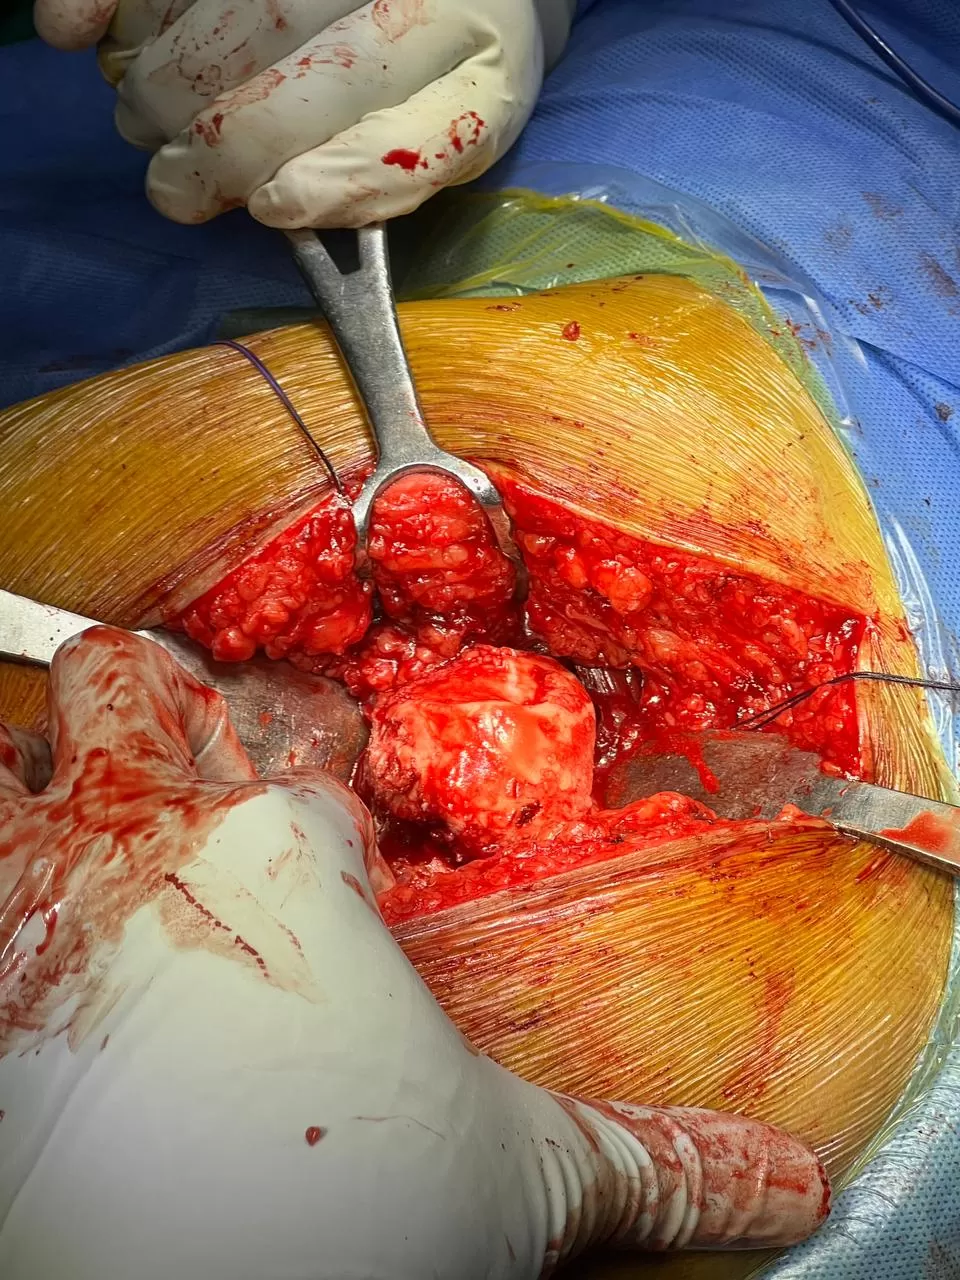

Hemlata

Name: Hemlata

Date of Operation: 7 November 2025

Age: 40 Years

Complex Trauma